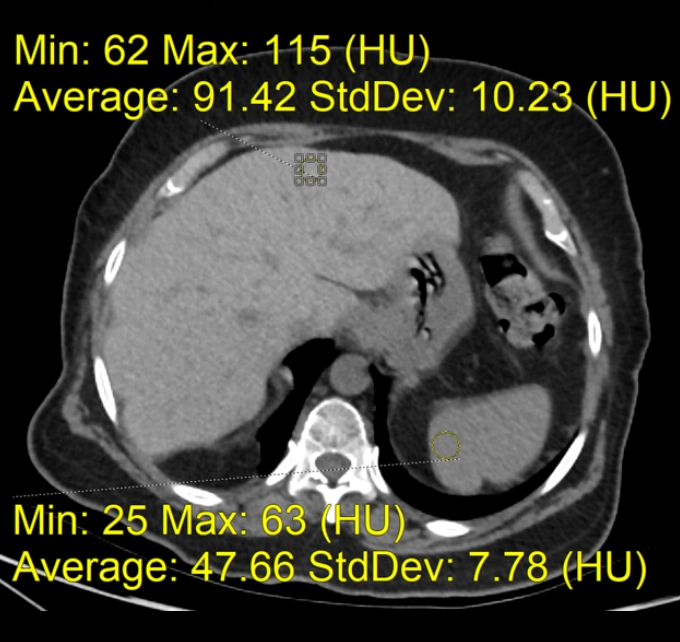

• Gan nhiễm mỡ (Steatotic liver disease)

• Gan nhiễm mỡ khu trú (Focal hepatic steatosis)

• Gan nhiễm mỡ lan tỏa (Diffuse hepatic steatosis)

• Lắng đọng amiodarone trong gan (Amiodarone deposition in the liver)

• Xơ gan (Cirrhosis)

• Gan ứ đọng sắt (Hemochromatosis)

• Gan to (Hepatomegaly)